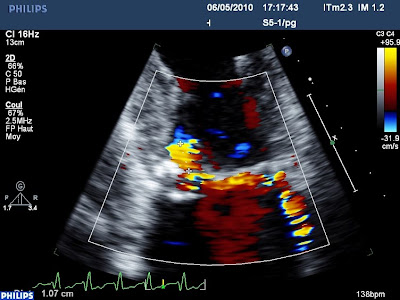

IM commissurale postérieure

70 ans, OAP, Gros souffle d’IM, mais une ETT peu informative. On devine un jet très excentré, avec une PISA, naissant d’une zone commissurale postérieure très calcifiée avec un cône d’ombre postérieur (la partie postérieure de l’anneau est massivement calcifiée). En ETO 3d, on confirme la présence d’un prolapsus de la commissure postérieure (a droite de l’image), qui est figée dans la calcification. La fonction i-sclice permet de découper le volume 3d acquis selon de coupes parallèles dont ont peu régler l’épaisseur et l’orientation sur les trois plans de l’espace. Quand on s’oriente parallèle à l’anneau mitral, on retrouve bien le prolapsus commissural (en haut sur l’image) avant le plan de l’anneau, figée dan l’OG. On aurait peut-être compris le mécanisme de cette fuite sans le 3d, mais ces fonctions permettent de passer du gros doute à une affirmation. Inutile d’insister sur l’outil de communication, les « non initiés » comprennent enfin de quoi on parle!